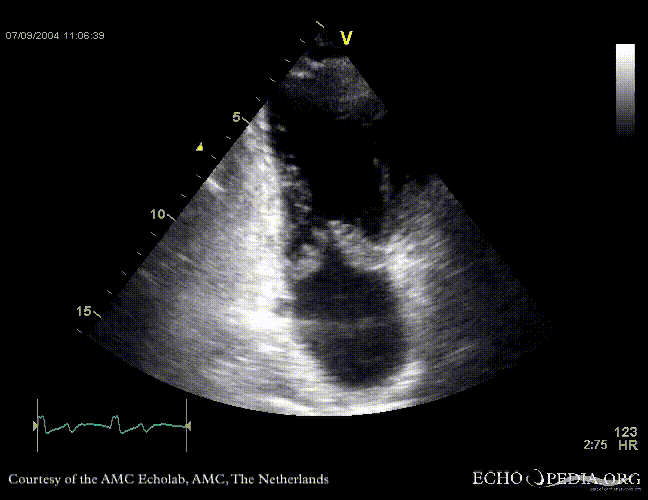

Case 11

| Courtesy of: J. Vleugels, AMC, The Netherlands | |

| Sarcoidose 2 | Sarcoidose 5 |

| Sarcoidose 7 | Sarcoidose 8 |